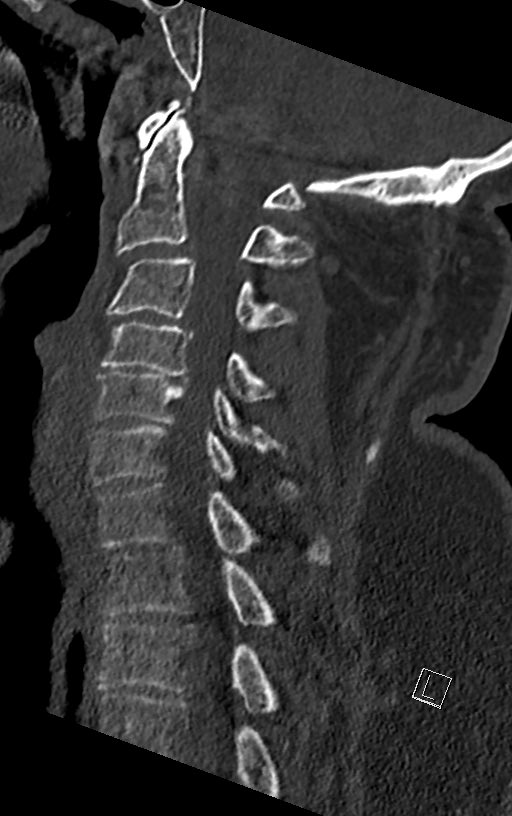

odontoid fracture type II:

epic controversial discussions, how to treat them in the elderly, when #comorbidity index is high.

this is a #odontoid process/dens axis in a patient with radiculomyelopathy.

osteoarthritis of the atlantodental joint is present, too

4 years later (after ACDF), he fell and sustained odontoid fracture type II according to Anderson/d’Alonzo. you see the fracture line - and no, it’s not “incomplete”, it’s for sure complete, just the positioning in the CTscan. As pain was no problem, we’ve put him in a collar

what would you have recommended in this 68yo patient if he was in your hospital?